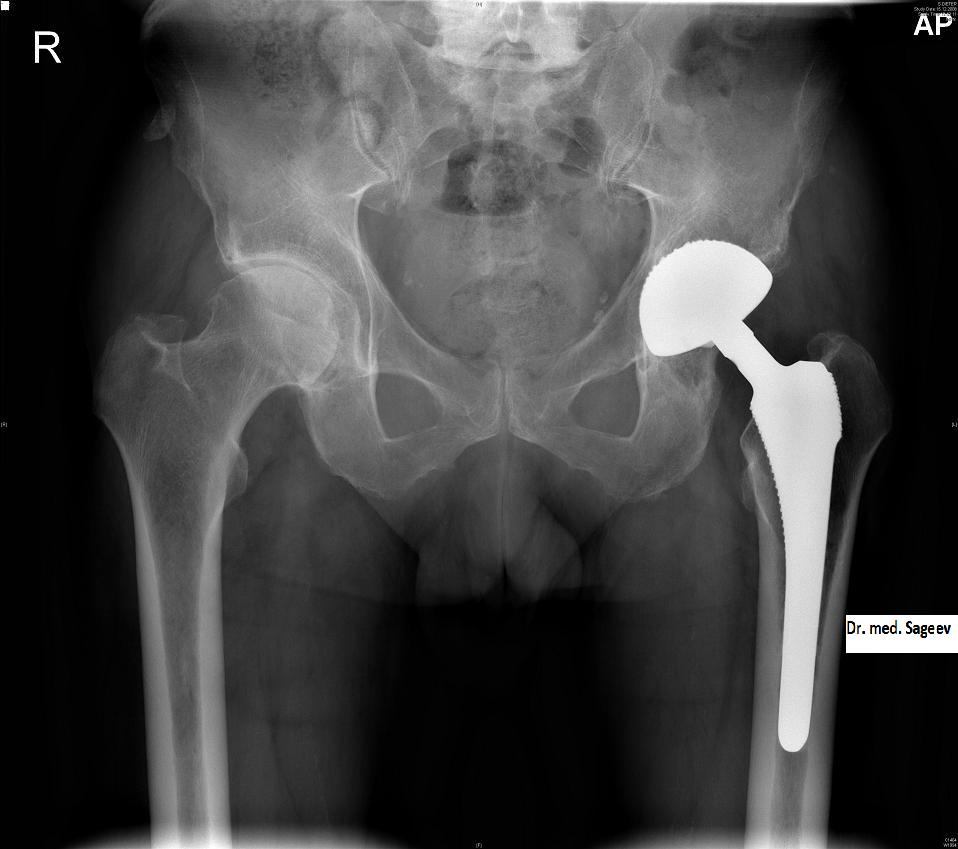

"ломает пожилой человек шейку бедра (самая распространенная травма) – это на 150 тысяч минимум он уже попал"

Понятно, что расходы у пациентов вырастут очень серьезно. Вот схватило у человека спину. Надо снять боль, провести диагностику, физиотерапию, мануальную терапию. За все про все – выйдет тысяч 30. А если, не дай бог нужна операция – то на порядок больше. Эндопротезирование тазобедренного сустава, допустим – от 150 до 300 тысяч, в зависимости от стоимости протеза. То есть ломает пожилой человек шейку бедра (самая распространенная травма) – это на 150 тысяч минимум он уже попал. Или поиграл в футбол, травмировал мениск или связку в колене – от 50 до 150 тысяч. Это не считая реабилитации. Нужна лечебная физкультура, ортопедические устройства на сустав и т.д.

эндопротез

Не каждый пенсионер сможет позволить себе поставить эндопротез за 300 тысяч рублей